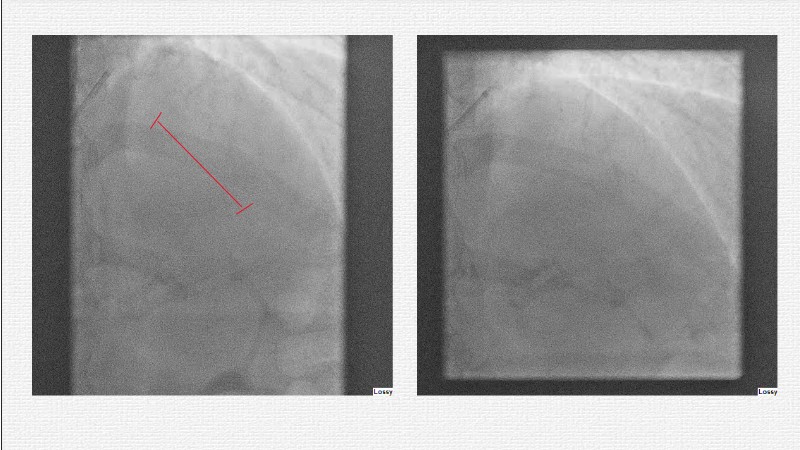

This EuroPCR 2025 session challenges the conventional approach to bifurcation PCI and dissection management. Learn why drug-coated balloons (DCB) may offer better long-term outcomes in cases where stents fall short, how DCBs can simplify bifurcation strategies, and why it’s time to rethink which dissections really need stenting. Through data, case examples, and clear decision-making insights, you'll gain the confidence to broaden your DCB practice where it truly matters.

- To evaluate which dissection to leave and which to stent